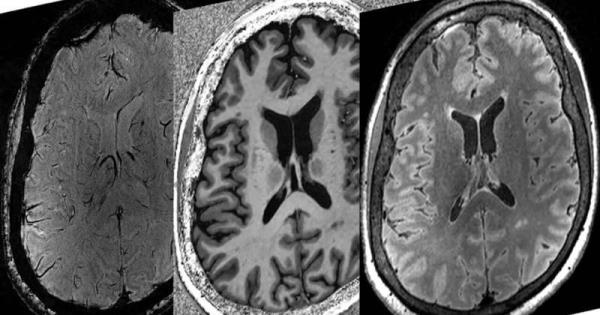

Matthew Kolisnyk和Karnig Kazazian将功能磁共振成像(fMRI)与最先进的机器学习技术相结合,解决了重症监护中最复杂的问题之一。

该团队在伦敦两家重症监护室之一的25名患者严重脑损伤后的头几天测量了他们的大脑活动,并测试了它是否能预测谁能活下来,谁不能。

诺顿说:“我们之前发现,这些患者康复潜力的信息是通过不同大脑区域相互交流的方式获取的。”“大脑区域之间完整的交流是恢复意识的重要因素。”

当团队意识到他们可以将这种成像技术与被称为机器学习的人工智能应用相结合时,突破就出现了。他们发现,他们能够以80%的准确率预测病人的康复情况,这比目前的护理标准要高。